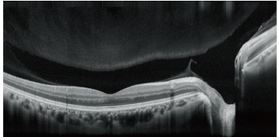

1.高清晰的OCT可进行广域扫描(12 x 9 mm),具备SLO功能

高清晰的OCT可进行广域扫描(12 x 9 mm),具备SLO功能

12 mm水平扫描可在单幅图像上观察从黄斑到视盘的宽大区域。